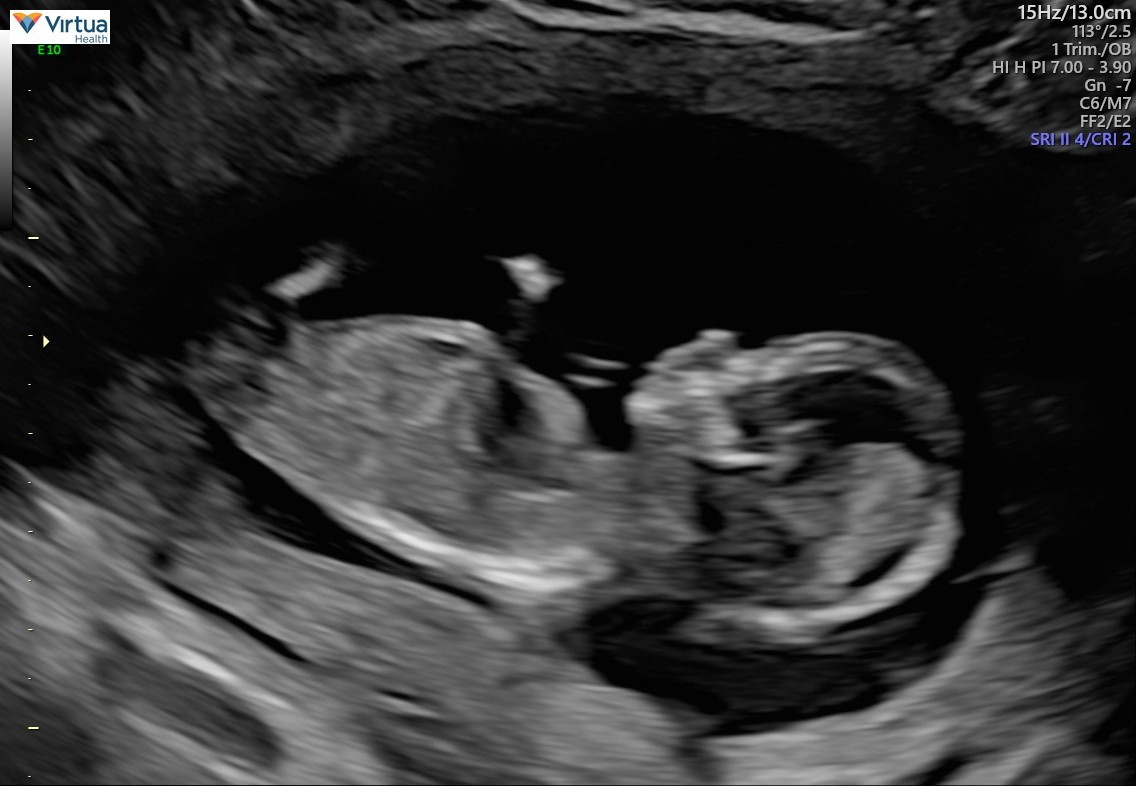

finally a freaking ultrasound! had my NT scan yesterday at 11 weeks 6 days! now just waiting for my Panorama results!